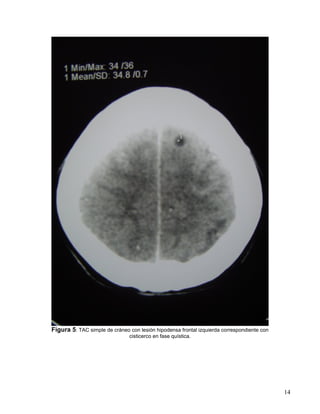

-Simple de cráneo con lesión hipodensa frontal izquierda correspondiente con cisticerco en

fase quística (fig. 5)

Figura 5: TAC simple de cráneo con lesión hipodensa frontal izquierda correspondiente con

cisticerco en fase quística.